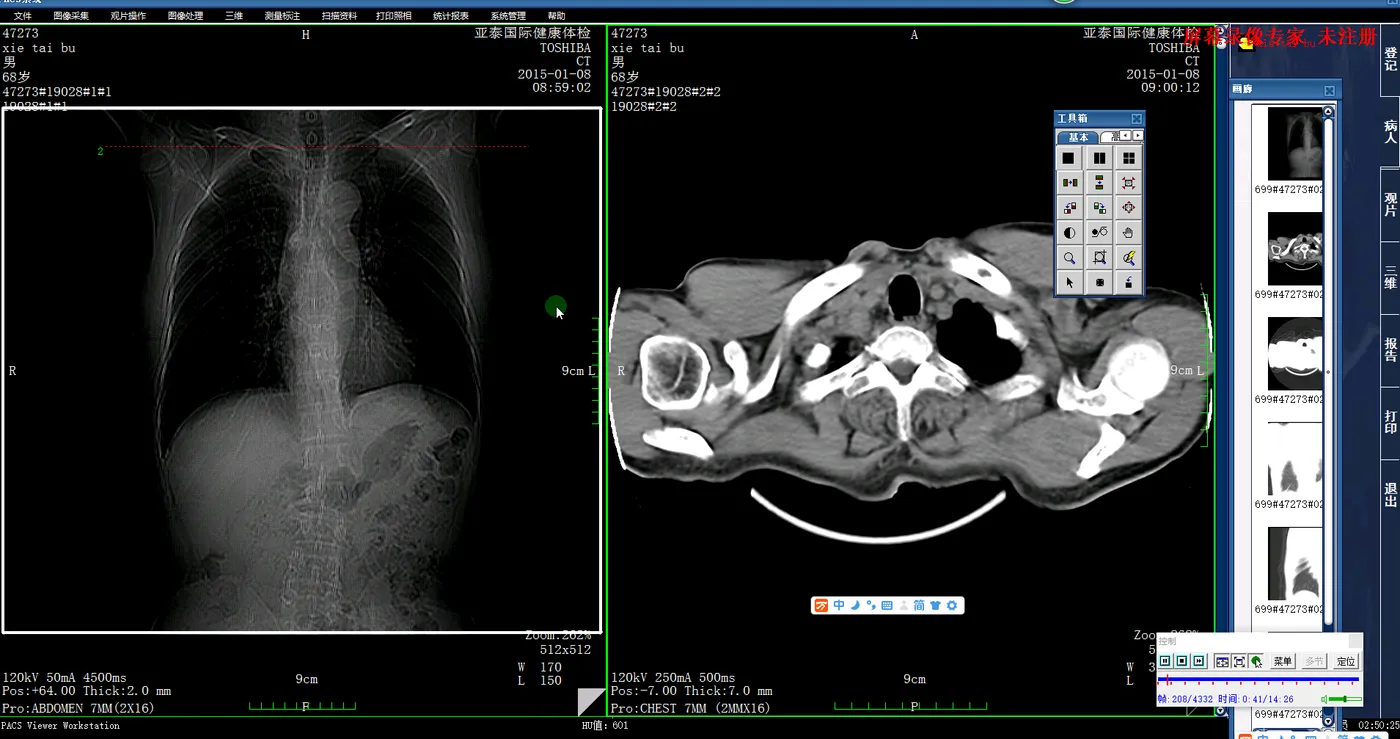

诊断工作站:供放射科医生使用的专业高分辨率显示器电脑,用于浏览、分析、处理影像并撰写诊断报告。

图像显示与处理:提供强大的工具供医生浏览、缩放、测量、三维重建图像。